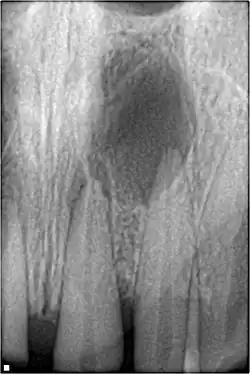

- Radiographic signs of periapical inflammation

Pulpal obliteration

4–24% of traumatized teeth will have some degrees of pulpal obliteration that is characterized by the loss of pulpal space radiographically and yellow discolouration of the clinical crown. No treatment is needed if it is asymptomatic. Treatment options will be extraction for symptomatic primary tooth. For symptomatic permanent tooth, root canal treatment is often challenging because the pulp chamber is filled with calcified material and the drop-off sensation of entering a pulp chamber will not occur.[44]